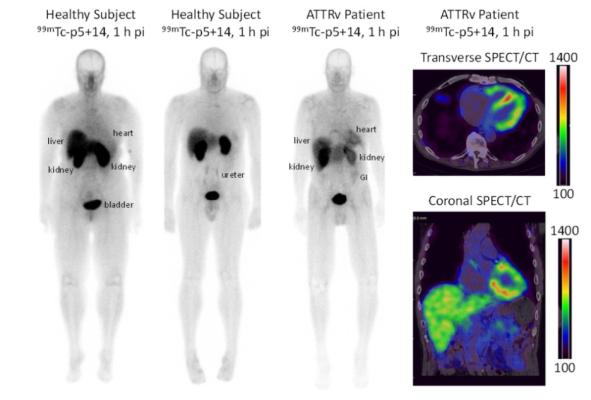

Atlases of Tumor & Non-Tumor Pathology, 5th Series, Fascicle 17 - Disorders of Heart & Blood Vessels: 洋書/南江堂, Novel Radiotracer Produces High Quality Images of “Alzheimer's Disease of the Heart” | Imaging Technology News,

Novel Radiotracer Produces High Quality Images of “Alzheimer's Disease of the Heart” | Imaging Technology News, Cardiac Autonomic Dysfunction and Incidence of Atrial Fibrillation: Results From 20 Years Follow-Up - ScienceDirect,

Cardiac Autonomic Dysfunction and Incidence of Atrial Fibrillation: Results From 20 Years Follow-Up - ScienceDirect, Atrial electrofunctional predictors of incident atrial fibrillation in cardiac amyloidosis - Heart Rhythm

Atrial electrofunctional predictors of incident atrial fibrillation in cardiac amyloidosis - Heart Rhythm